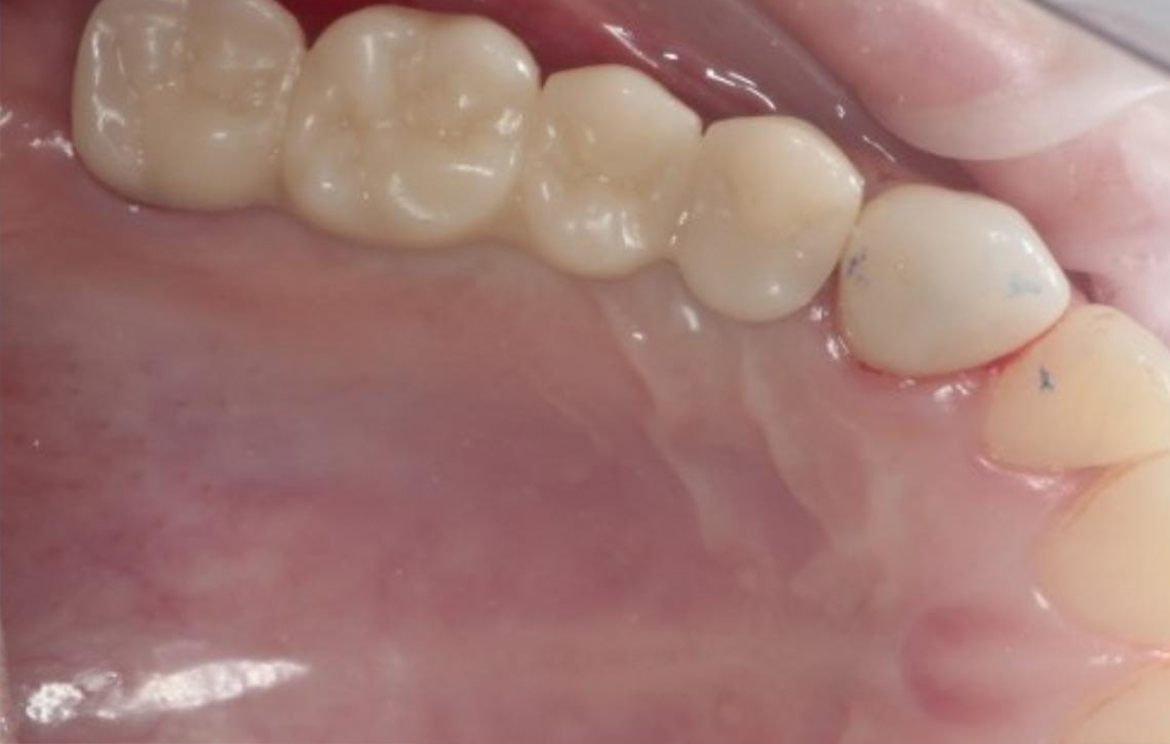

Наши работы